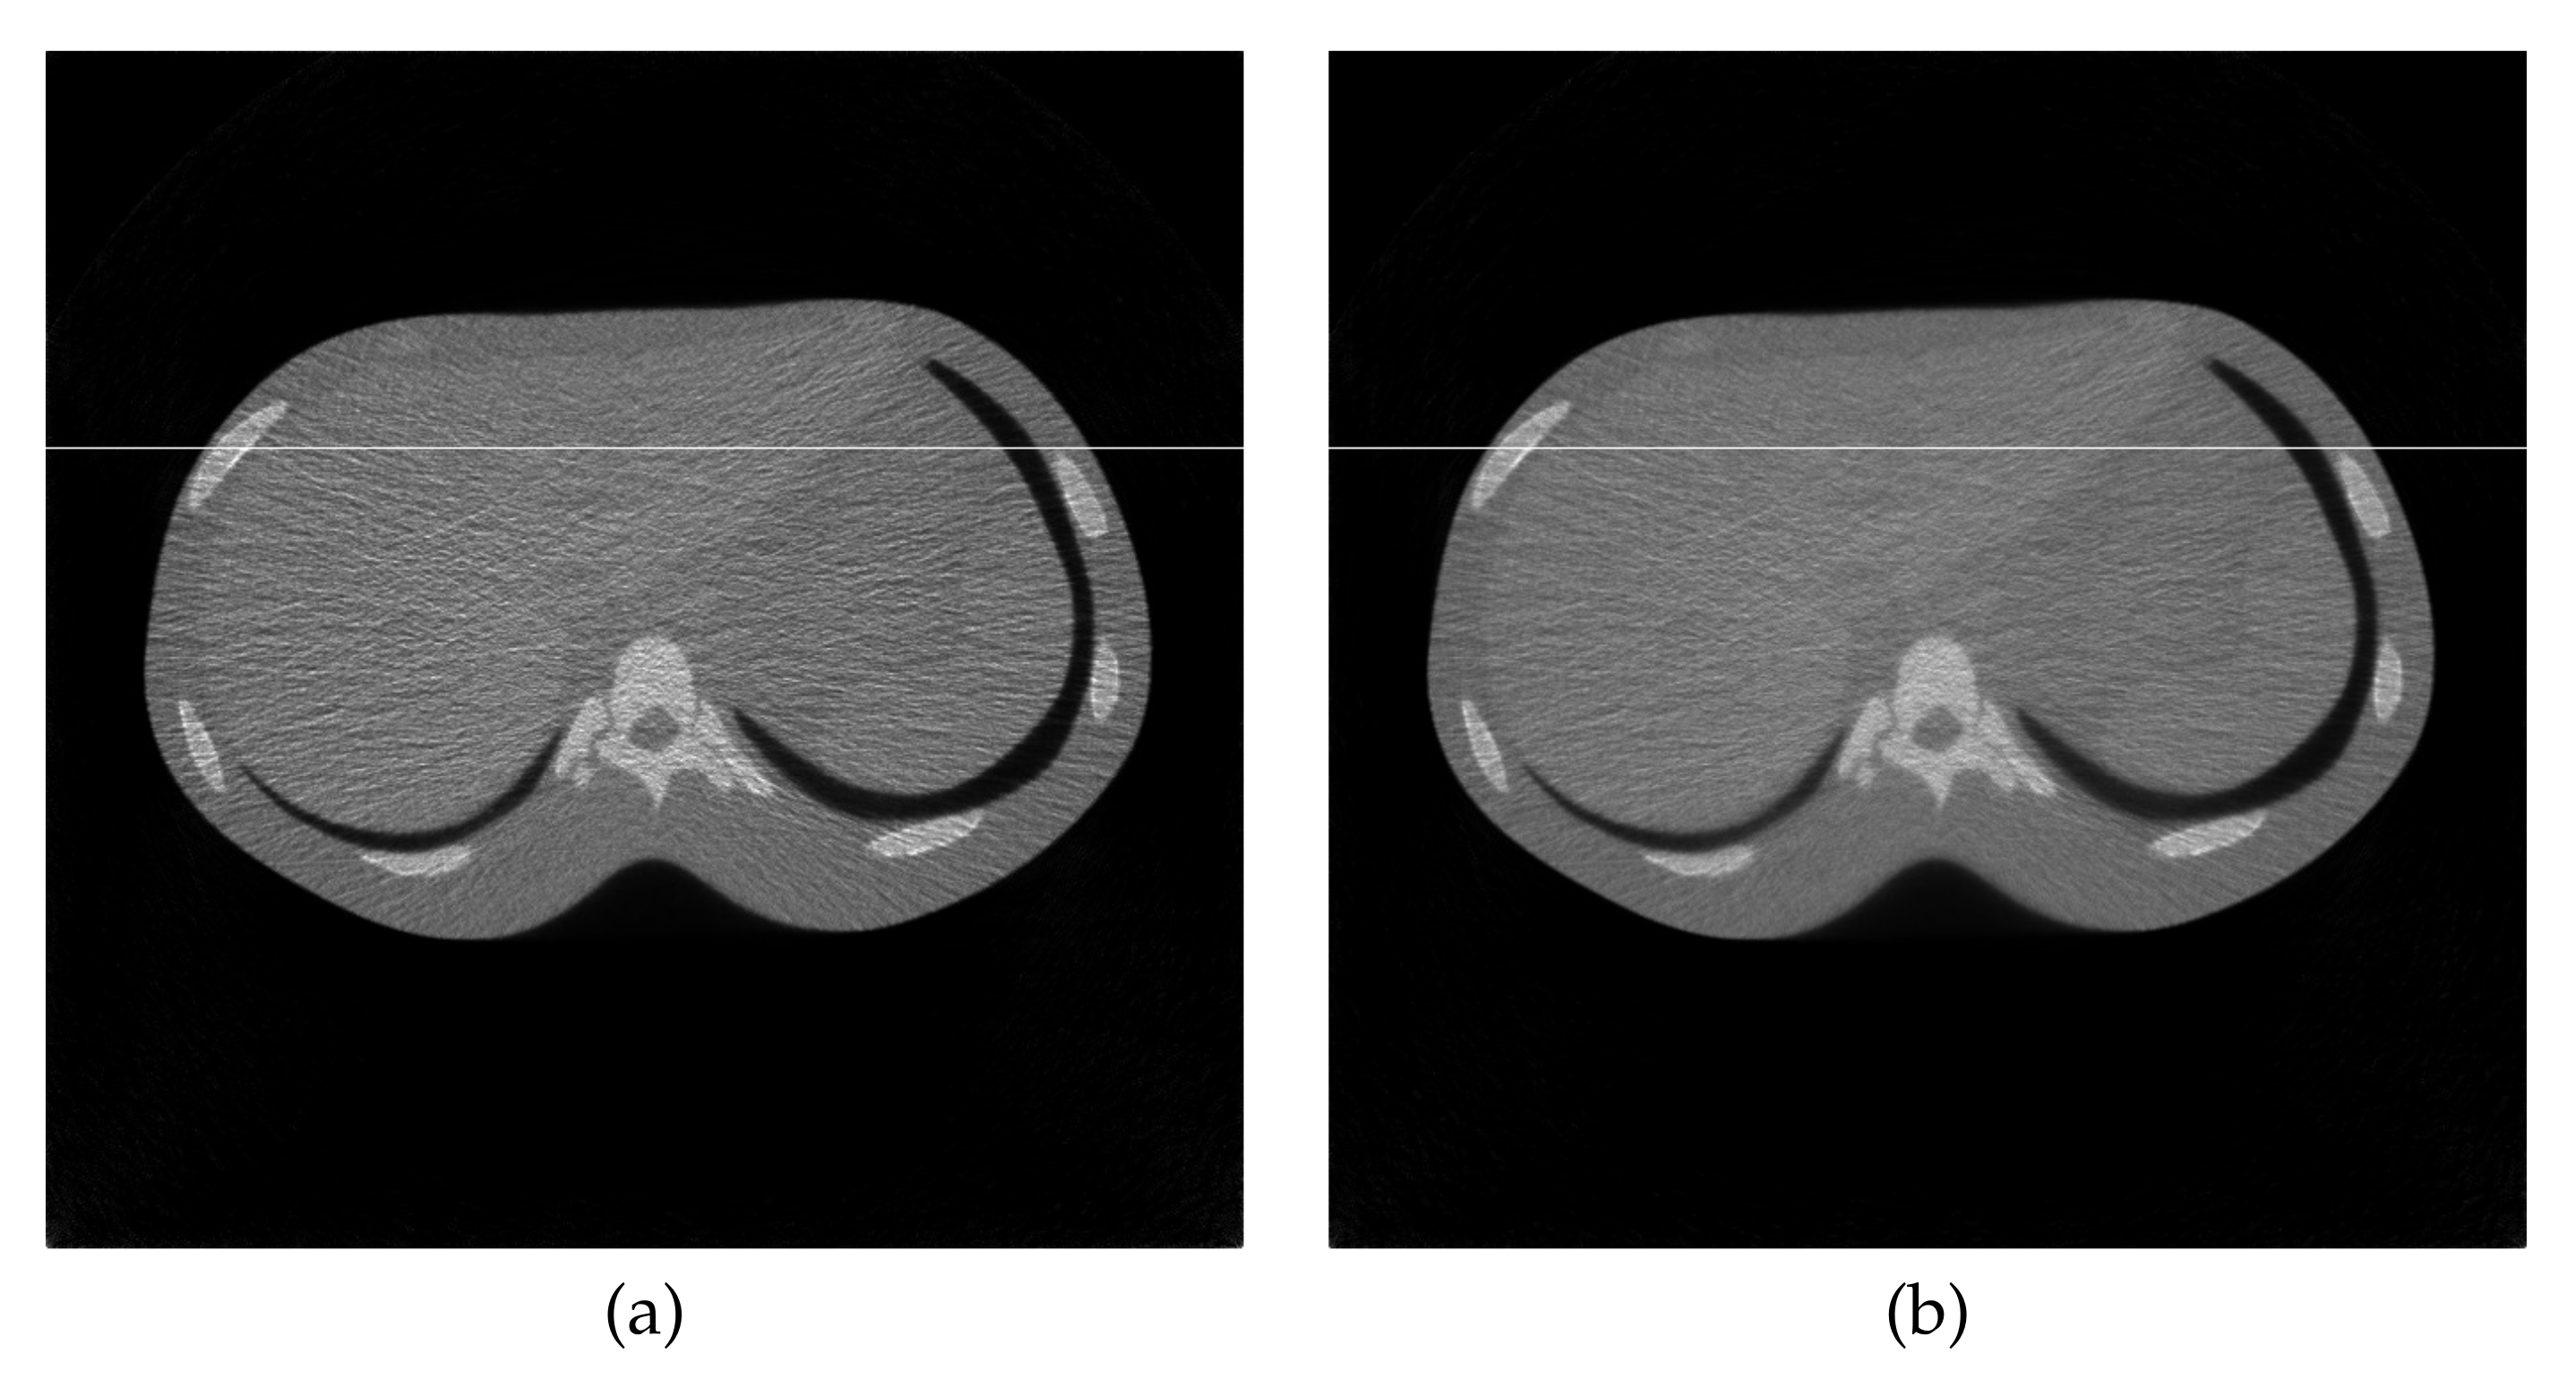

4.2. Reconstruction Using Physical Phantom